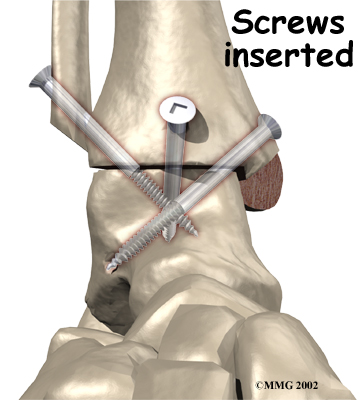

It is important when the surfaces are removed that the angles of the cut surfaces are correct. When the tibia is brought against the talus, the foot should be at a right angle to the lower leg. Once the cuts are made, the bones must be held in place while they fuse. This can be done using large metal screws and metal plates if necessary. The screws are usually under the skin and are not removed unless they begin to rub and cause pain.

Inserting the screws